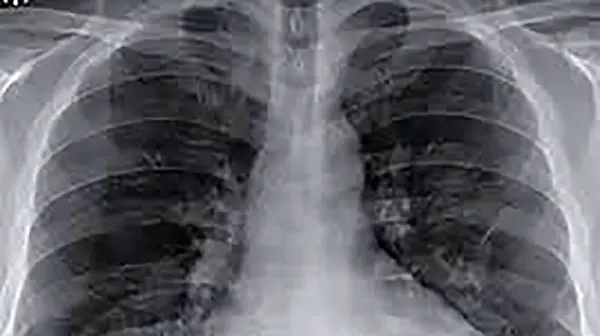

از کجا بفهمیم ریه های مان درگیر کرونا شده؟

به گزارش رکنا ، مسعود مردانی فوق تخصص بیماریهای عفونی در پاسخ به این سوال که در صورت ابتلا به کرونا چگونه بفهمیم ریههایمان درگیر شده؟، گفت: چنانچه بیمار مبتلا به کرونا احساس تنگی نفس داشته باشد و روی قفسه سینه احساس فشار کند و همچنین هنگام راه رفتن دچار مشکل شود، احتمالا دچار درگیری ریوی شده است.

عضو کمیته علمی ستاد کرونا ضمن اشاره به اینکه در صورتی که بیماری با این علائم رو به رو بود حتما باید مراکز درمانی مراجعه کند تا اکسیژن خون او گرفته شود، افزود: چنانچه سطح اکسیژن خون بیمار کمتر ۹۳ باشد، پزشک معالج در خواست سیتی اسکن و عکس ریه میدهد و مشخص میشود، میزان درگیری ریوی بیمار به کرونا چه قدر است.

حمید عمادی در این خصوص بیان کرد: بیماران مبتلا به کرونا که دچار علائمی نظیر تنگی نفس و احساس درد و سنگینی در قفسه سینه باشند و همچنین مدام نسبت به هوا احساس عطش داشته باشند، به احتمال زیاد درگیری ریوی پیدا کرده اند و باید هر چه سریع به پزشک مراجعه کنند.

وی همچنین در پاسخ این سوال که آیا ممکن است بیمار بدون علائم خاصی دچار درگیری ریوی شده باشد؟ ادامه داد: گاهی اوقات ممکن است چنین اتفاقی رخ دهد و این اتفاق بیشتر برای بیمارانی که درگیری ریوی خفیفی دارند، میافتد و اغلب درگیریهای وسیع و خطرناک با علائم همراه هستند.آخرین قیمت های بازار ایران را اینجا کلیک کنید.